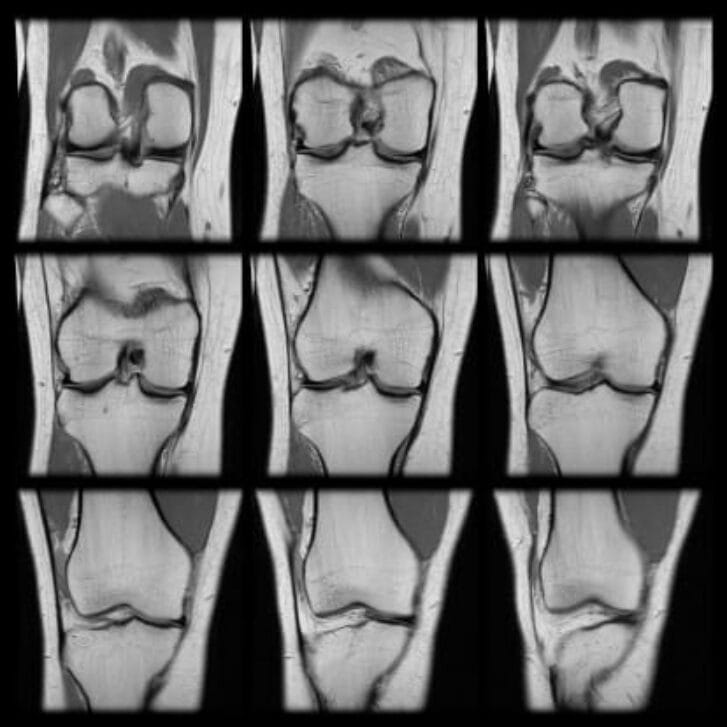

Innovative medical products help wipe away the ugly vision of unnecessary health care.